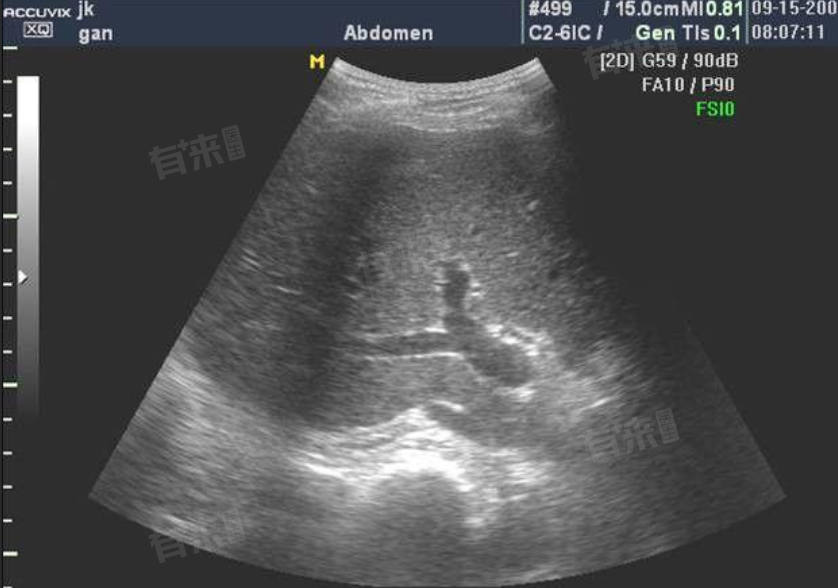

肝回声细密是肝脏超声检查中的一种表现,意味着肝脏内部结构发生了变化,其背后可能潜藏着多种肝脏疾病,包括脂肪肝、肝炎、酒精性肝病等。

此外,肝硬化是肝脏疾病的严重阶段,往往由长期的肝损伤发展而来。肝细胞广泛坏死,肝脏进行反复的修复与重建,形成假小叶结构。肝脏的质地变硬,结构紊乱,超声检查表现为回声细密,且常伴有肝脏形态的改变。患者可能出现腹水、食管胃底静脉曲张等严重并发症。

- 在影像学方面,肝脏弹性检测通过测定肝脏硬度,评估肝纤维化程度。腹部CT或MRI检查能更清晰、全面地观察肝脏的形态、结构,排查有无占位性病变等其他异常情况,为准确诊断提供有力依据。